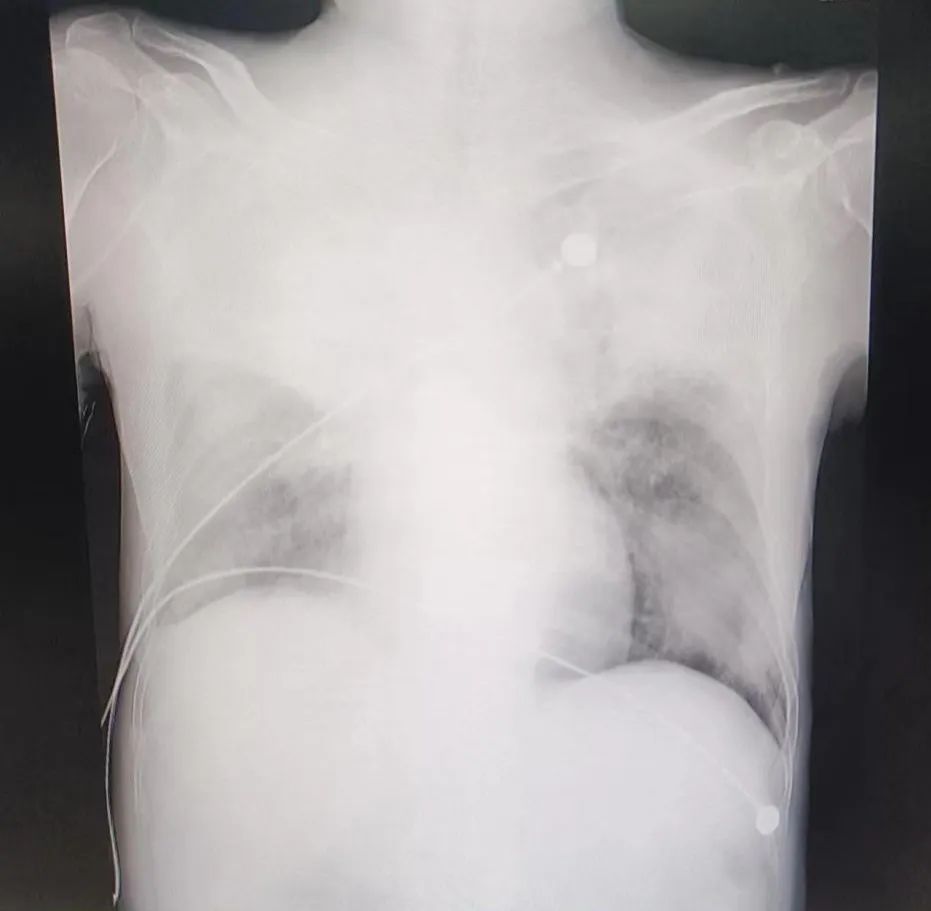

随着新冠开放,身边“阳了”的人越来越多,青壮年纷纷“倒下”、高烧、感冒、肌肉酸痛、咳嗽痰多......,一般5-7天开始好转,而老年人身体机能逐步下降,基础疾病多,抵抗力差,感染新冠后机体异常的反应可能不会像年轻人那样明显。比如有些老年人已经体温升高了,却不知道自己发烧。此外,老年人感染新冠后有可能会发生“沉默性低氧”,家人觉得他的呼吸状态似乎还挺平稳,但血氧饱和度可能已经比较低了。近日,玉林市中西医结合骨科医院重症医学科在党支部书记、科主任钟瑜的带领下,克服各种困难,收治了多例感染新冠病毒的老年病人,这些病人往往在转进重症监护室时,病情已经很严重,血氧饱和度极低,呼吸困难,需要呼吸机辅助呼吸了,通过肺部影像可以看到这些病人的肺部出现了“白肺”。什么是“白肺”?“白肺”一般指重症肺炎患者在X光或CT检查下的表现,肺部显影呈一大片的白色状而得名。医务人员跟老百姓所说的"白肺",是说患者肺炎较重,渗出液较多,预示着肺部被炎症广泛浸润。通常认为肺部影像学白色面积达到70%以上,在临床上称它为白肺。此时,俯卧位通气,是一种治疗急性呼吸窘迫综合征的辅助措施。俯卧位通气指的是病人采取俯卧位的体位进行机械通气的一种方法。该通气方法主要适用于重症肺部疾病如急性呼吸窘迫综合征的病人,经过高强度的呼吸机支持仍不能维持正常人体所需要的氧合。实践证明,这种通气方式的有利于靠近背部的肺进行血气交换,改善氧合,促进患者康复,在我院救治中取得了良好的效果。